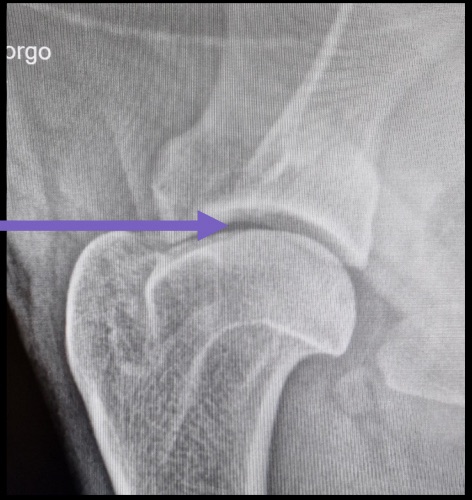

La locomotion est objectivée avec les différents paramètres mesurés à l’aide de l’outil Tendiboots™ Canine. Des examens radiographiques et échographiques ont également été effectués sur Kara.

![]() |